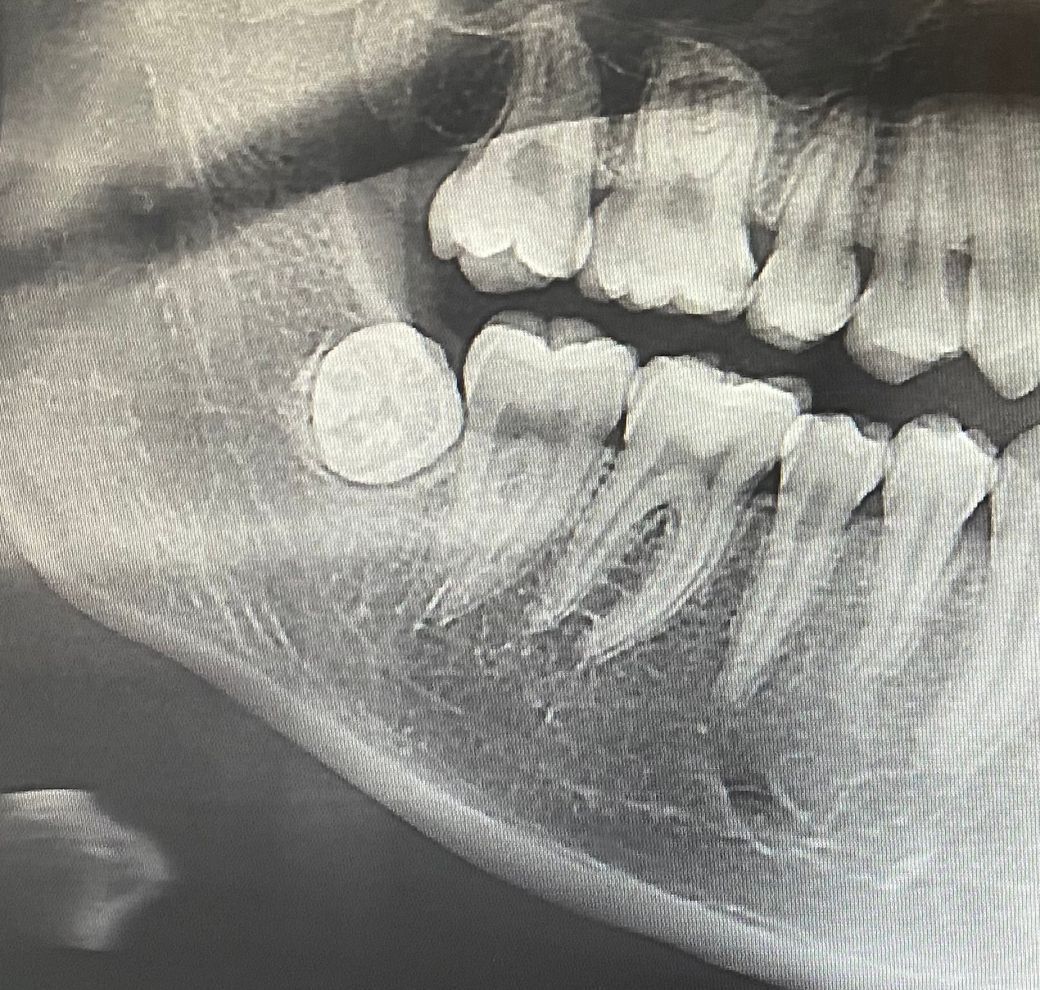

왼쪽 아래 사랑니를 뽑아보니 너무 아파서 오른쪽은 뽑기 망설여지는데 이렇게 자란것도 뽑아야하나요? 튀어나오지는 않았습니다.

해당 사랑니는 완전 매복 사랑니이고 뽑고자 한다면 잇몸을 절개하고 일부 뼈를 쳐내고 사랑니를 분할하여 뽑게 됩니다. 현재로선 특별히 불편함이 없다면 반드시 발치가 필요하진 않은 상태입니다.

x-ray상 사랑니를 보아, 현재 반드시 뽑아야 하는 상태는 아닌 것 같습니다. 그렇지만 아주 깊게 묻히지는 않아서 나중에 염증이 생길수도 있고, 그 때는 발치를 하는 것이 좋습니다.

현재 매복사랑니로 보이며 이를 방치하는 경우 통증 없다고 두면 바로 앞 어금니가 서서히 상하게 되어 사랑니와 어금니를 함께 뽑아야할수 있습니다. 따라서 가능한 빠른시일내에 발치를 권합니다.